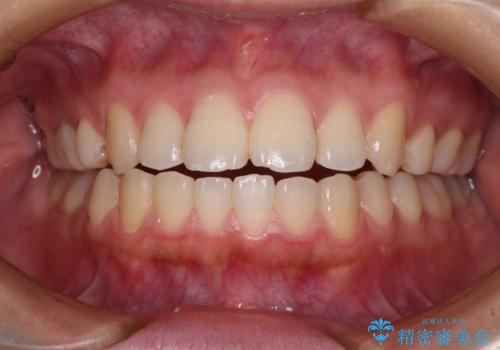

外側に飛び出した歯 インビザラインによる矯正治療

治療途中で1年半以上通院されない時期があったため、後戻りが生じたことで治療期間が長くなってしまいました。

親知らずを抜去したことで、下顎のデコボコがきれいに解消されました。